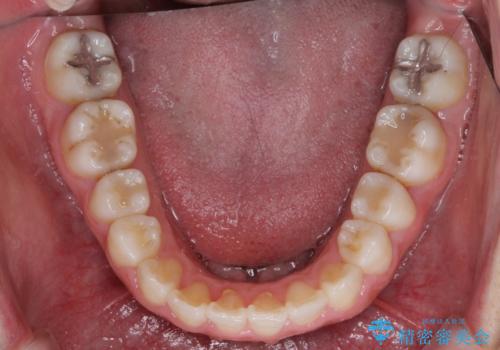

- ワイヤーではない矯正治療があると聞いたとのことで来院された患者様です。

長年前歯のデコボコを気にしていたもののワイヤー矯正に抵抗があり躊躇していたそうですが、インビザラインなら治療してみたいとのことで相談にいらっしゃいました。

インビザライン適用の歯列であったため、歯と歯の間を削るIPRを用いて改善することとしました。

お仕事柄、長時間のマウスピース装着が苦ではなかったので、歯列はすぐに整いましたが、ゆっくりとした交換頻度であったので、2年ほどの治療期間を要しました。